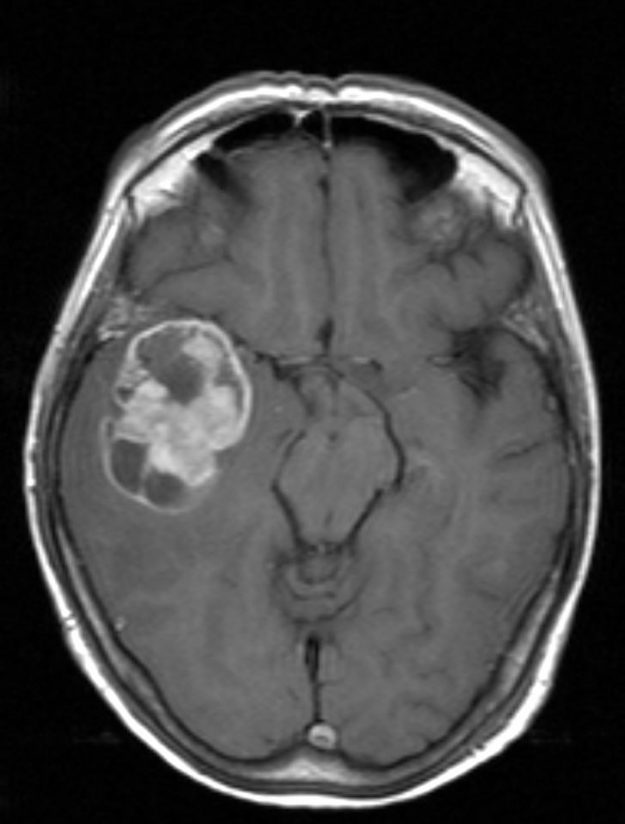

Ασθενής γυναίκα 58 ετών με πονοκεφάλους και διαταραχές όρασης. Ο οφθαλμολογικός έλεγχος έδειξε οίδημα οπτικών θηλών άμφω και σημαντικό περιορισμό των οπτικών πεδίων. Τα συμπτώματα της ασθενούς ήταν προοδευτικά επιδεινούμενα, το ίδιο και οι εξετάσεις της. Η μαγνητική εγκεφάλου ανέδειξε ευμεγέθη αραχνοειδή κύστη δεξιά κροταφικά με σημαντική πίεση επί του υγιούς εγκεφάλου και παρεκτόπιση των…